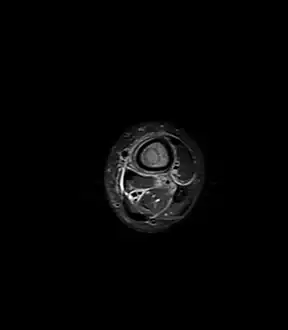

Axial T1-weighted fat-saturated MRI image following IV gadolinium contrast demonstrating the intramedullary lytic area seen on radiography to be ring enhancing consistent with a purulent fluid collection. Extensive circumferential periosteal enhancement is noted. There is also substantial bone marrow enhancement. -

Sagittal T1-weighted fat-suppressed post gadolinium image showing the extent of the multiloculated intramedullary abscess.